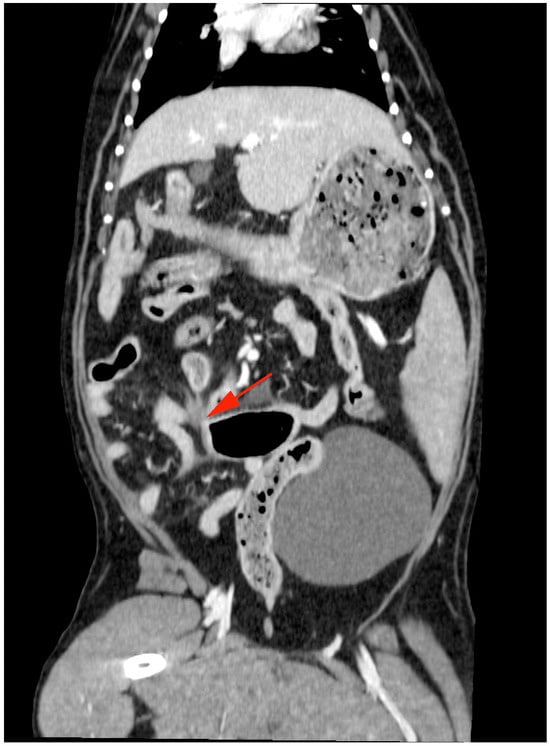

The dog was premedicated with a 5 ug/kg IV fentanyl bolus and anaesthesia induced with alfaxalone IV to effect. Anaesthesia was maintained with isoflurane and oxygen. Initial tachycardia was noted after induction, which resolved without medical intervention. Computed tomography (CT) was performed using a 16-slice helical scanner (GE Optima, Chicago, IL, USA) with a slice thickness of 1.25 mm, pitch of 0.938, rotation time of 0.8 s, 120 kVp, and 300 mAs. The patient was positioned in dorsal recumbency, and pre- and post-contrast (2 mL/kg IV iohexol) images of the thorax and abdomen were performed. All CT studies were submitted for review by a board-certified radiologist. There was a long (approximately 14 cm) moderately dilated segment of jejunum, which contained gas and mixed heterogeneous gas and soft tissue attenuating material (Figure 2, blue arrows). The caudal aspect was most significantly dilated, contained more gas, and tapered abruptly (Figure 3, red arrow). There was mild peritoneal effusion and fat stranding. The adjacent lymph nodes were moderately enlarged with an undulating outline and were hypoattenuating (Figure 3, yellow arrows). The stomach was mildly dilated with mixed material, the duodenum and pancreas were unremarkable, and there was a small amount of formed faecal material within the colon. There were no overt signs of an intestinal foreign body.

The typical presentation with strangulated intestine is consistent with an acute abdomen; however, clinical symptoms vary with the degree of vascular compromise and strangulation [2]. While microcirculatory changes within the intestines occur prior to clinical symptoms, the progression of symptoms and irreversible damage to the intestinal wall is often rapid [10]. Resection and anastomosis of non-viable intestines due to strangulation is common [3,4,5,6,7]. In contrast, the dog in this report was stable and initially responsive to supportive treatment with fluids and analgesia. Initial diagnostics included three view abdominal radiographs, which were not conclusive of an obstructive pattern, with a maximal intestinal diameter to midbody fifth lumbar vertebrae ratio of <2.4 [13]. Abdominocentesis of scant-free abdominal fluid was not consistent with a septic abdomen. Hence, the clinicians continued with medical management for 72 h prior to surgical intervention. Computed tomography (CT) has been suggested to be more sensitive than radiographs for identifying mechanical intestinal obstruction [14] and was diagnostic in this case (Figure 3, red arrow). Despite the prolonged duration of strangulation, the incarcerated region of the jejunum was subjectively viable at surgery, with evidence of active haemorrhage and peristalsis [10]. This is likely due to the rent in the ventral median ligament being relatively large and partially impeding vascular perfusion of the affected jejunal segment.

Figure 3. Abdominal CT in the transverse plane displaying the caudal segment of dilated jejunum containing gas and tapering abruptly (red arrow).